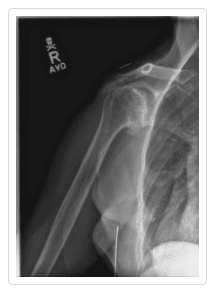

Osteoarthritis (degenerative joint disease) is an orthopedic injury that occurs when the cartilage that protects and allows the joints to move begins to wear down or degenerate, potentially causing the bones of the joints to scrape against one another with every movement. Shoulder osteoarthritis (OA) is a shoulder injury that is most common among people who are over the age of 50 after years of wear and tear on the joint. Younger adults experience osteoarthritis of the shoulder either as a result of hereditary predisposition or from an injury or trauma to the shoulder, such as dislocation. This arthritic condition is particularly common in people who work in jobs that require repetitive movements and physical activity, such as athletes or construction workers.

Total Shoulder Arthroplasty – A shoulder joint replacement surgery involves removing damaged bone and tissue and replacing them with artificial pieces or prosthesis. The procedure may involve only replacement of the head of the humerus bone or replacement of the entire ball and socket (glenoid) joint. The artificial components, made of metal or plastic, may be cemented into place or “press fit” into the socket if the bone is still in good condition.

Hemiarthroplasty – Also known as a partial replacement, a hemiarthroplasty involves replacing the humerus or arm bone with a prosthetic metal implant while the shoulder joint is left more or less intact. The shoulder osteoarthritis procedure may involve replacing the head of the humerus with a metal ball and stem as well as the arm bone or simply resurfacing the humerus head with a prosthesis that fits over the bone like a cap, preventing further wear and tear.